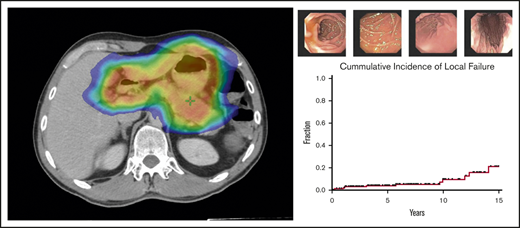

Treatment response to radiotherapy was assessed at 3 months by follow-up EGDs with multiple biopsies (Figure 2). Among the 166 patients who were treated for early-stage GML, posttreatment EGD with biopsy was performed in 160 patients, of whom 152 (95%) demonstrated a complete pathologic response (Wotherspoon 1-2) on the first posttreatment biopsy. Patients were serially followed by EGD biopsies in increasing intervals of 3 to 24 months.

EGD images documenting pathologic complete response. EGD images from patient 6, whose experienced spontaneous normalization without salvage treatment.

Over this extended follow-up period, 15 of 160 patients (9%) were found to have residual disease on EGD posttreatment biopsy (Wotherspoon 5; Figure 3). In addition, atypical lymphoid cells, not diagnostic of lymphoma (Wotherspoon 3-4), were described in 15 of 160 patients (9%). Six of the 15 patients (40%) with residual lymphoid cells subsequently progressed to local failure. Three of 20 patients (15%) with posttreatment residual disease experienced spontaneous resolution of their pathologic abnormalities on subsequent biopsy and, thus, were considered free of disease. The median interval from last radiation treatment to spontaneously resolved biopsy was 9 months (range, 8 months-3 years).

Natural history of EGD abnormalities. Fifteen patients who presented with early-stage GML exhibited residual GML on posttreatment EGD biopsy. Pathology review reported no evidence of disease (green circle), atypical lymphoid cells (blue circle), or residual GML (red open circle). Five patients with atypical lymphoid cells subsequently progressed to local failure (patients 2, 3, 4, 5, and 9). Three patients (6, 8, and 14) had pathologic EGD failures that self-resolved with observation alone.

Over a median follow-up of 6.2 years from the end of RT (range, 19.7 months-23 years), 12 of 166 patients (7%) treated for early-stage disease experienced local failures. Five-year and 10-year local failure rates, using death as a competing risk, were 3.9% and 8.3%, respectively (Figure 4). Median time to local disease failure was 4.4 years (range, 3 months-14 years). One patient who developed DLBCL of the stomach 1 year after RT was treated with cyclophosphamide, doxorubicin, vincristine, and prednisone (CHOP) chemotherapy and died of disease a year later. The remaining local relapses were associated with refractory GML on EGD biopsy. Salvage therapies included rituximab, additional radiotherapy, and rituximab (R)-CHOP.

Local and distant disease failures. Cumulative incidence of local and distant failures for patients treated for early-stage GML (N = 166), using death as a competing risk. Five-year and 10-year local failure rates were 3.9% and 8.3%, respectively, whereas 5-year and 10-year distant failure rates were 6.9% and 11%, respectively.